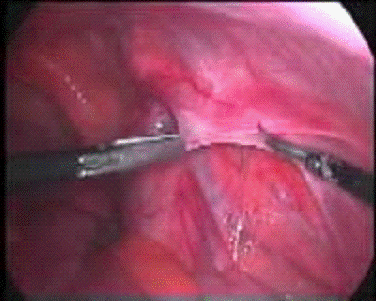

Рис. 3. Этапы операции по установке имплантата. Сшивание наружного края имплантата и наружной косой мышцы (Surgical Endoscopy, Hernia Treatment)